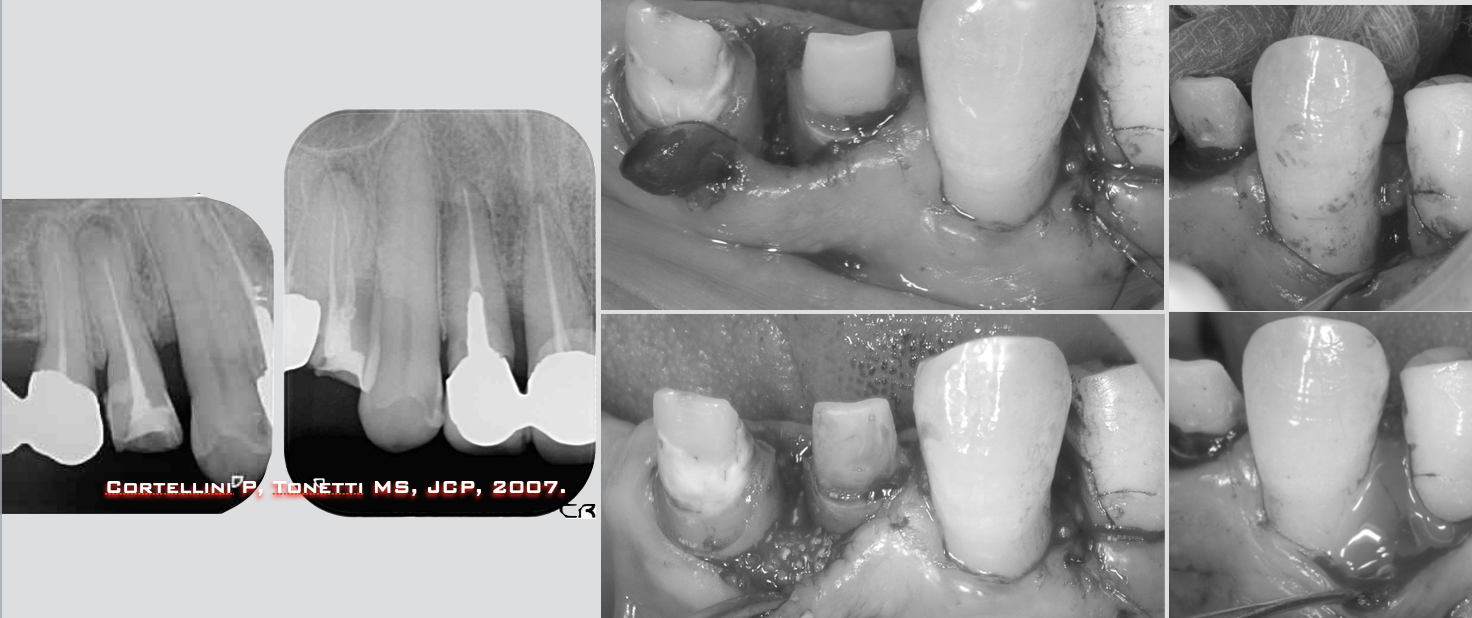

↑初診時のレントゲンを見てみましょう。局所的にかなり歯の周囲の骨が溶けているのがわかります。噛み合わせが原因の特異的な歯周病といえるでしょう。

重度に進んだ歯周病罹患歯は初期の治療だけでは改善しにくい場合がほとんどです。その歯に対して歯周組織再生療法を行なっていきます。

先ずは上顎の前歯と小臼歯に対して。結構難易度が高い歯と歯の間の骨が溶けた部位への治療です(上)。術後1年、良い状態に改善が見られます(下)。